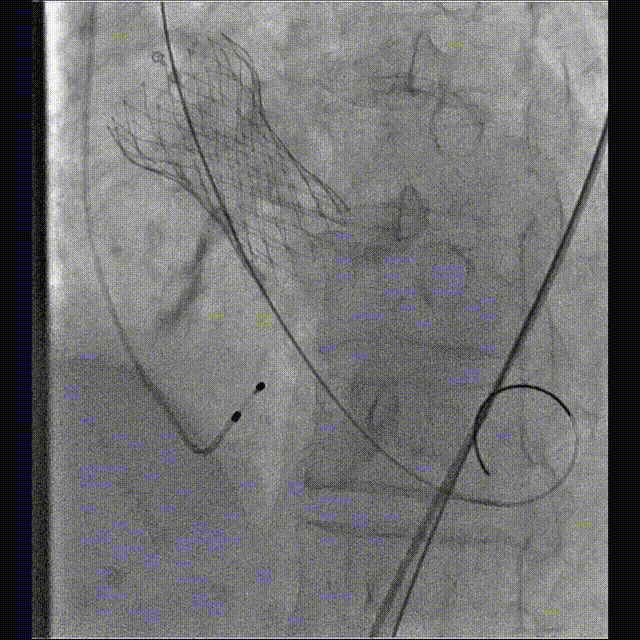

完全释放

术后超声提示无反流

术后压力